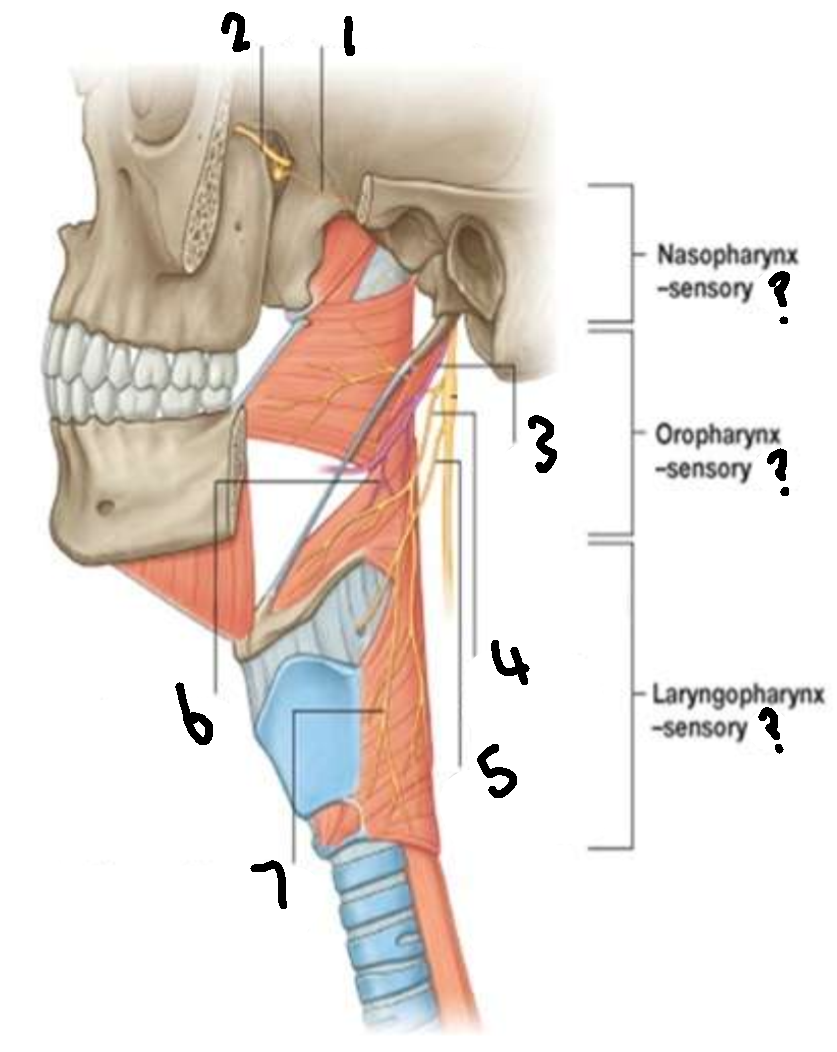

What provides sensory innervation to the nasopharynx?

mandibular branch of trigeminal V2

What provides sensory innervation to the oropharynx?

glossopharyngeal IX

What provides sensory innervation to the laryngopharynx?

vagus X

What is 1?

pharyngeal branch of V2

What is 2?

maxillary branch of trigeminal V2

What is 3?

glossopharyngeal IX

What is 4?

pharyngeal branch of vagus X

What is 5?

superior laryngeal nerve

What is 6?

pharyngeal branch of IX

What is 7?

external laryngeal branch of superior laryngeal nerve of X